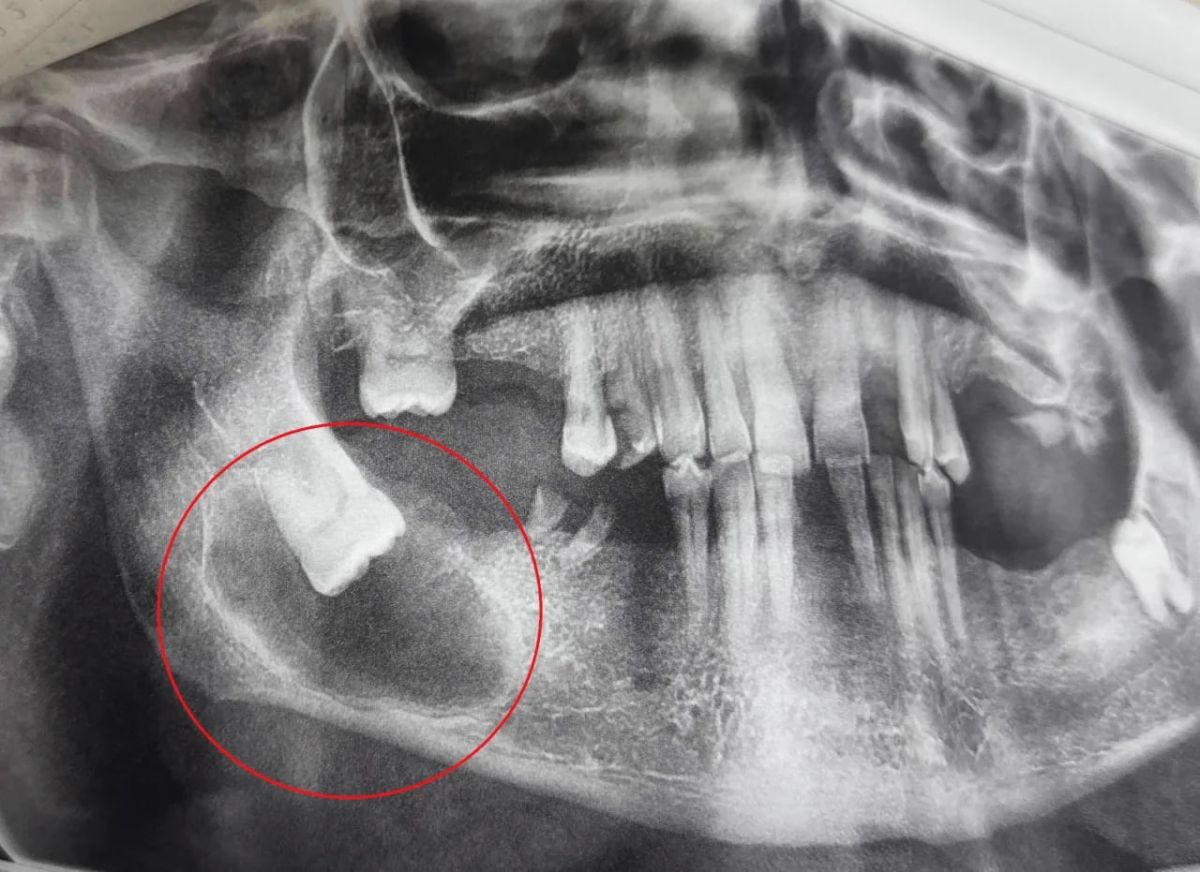

Комплексное обследование выявило серьезную проблему: непрорезавшийся зуб мудрости лежал горизонтально, а вокруг его коронки и части корня сформировалась фолликулярная киста, которая привела к снижению плотности костной ткани. Кортикальная пластинка оказалась истончена, однако признаков острого воспаления не наблюдалось.

Пациенту потребовалось хирургическое вмешательство. Операцию провела стоматолог-хирург Анастасия Асеева. Под местной анестезией врач сделала разрез, отслоила слизисто-надкостничный лоскут и обнажила кортикальную пластинку. Обнаружив истончение кости, специалист выполнила трепанацию – создала отверстия для доступа к патологическому очагу. После удаления самого зуба мудрости последовал самый ответственный этап – цистоэктомия. Хирург полностью удалила оболочки кисты и выскоблила измененные патологические ткани.